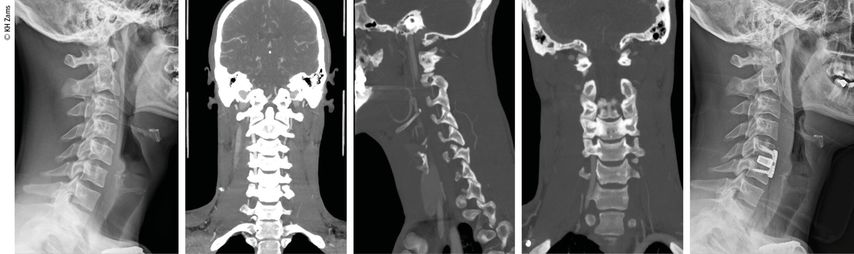

Abb. 3: Mann, 30a, Z.n. Snowboardsturz, Rotations-/Subluxationsverletzung C5/6 mit Dissektion der A. vertebralis r.; Zervikobrachialgie mit sensiblem Defizit; OP unter Heparintherapie, APT für 3 Monate